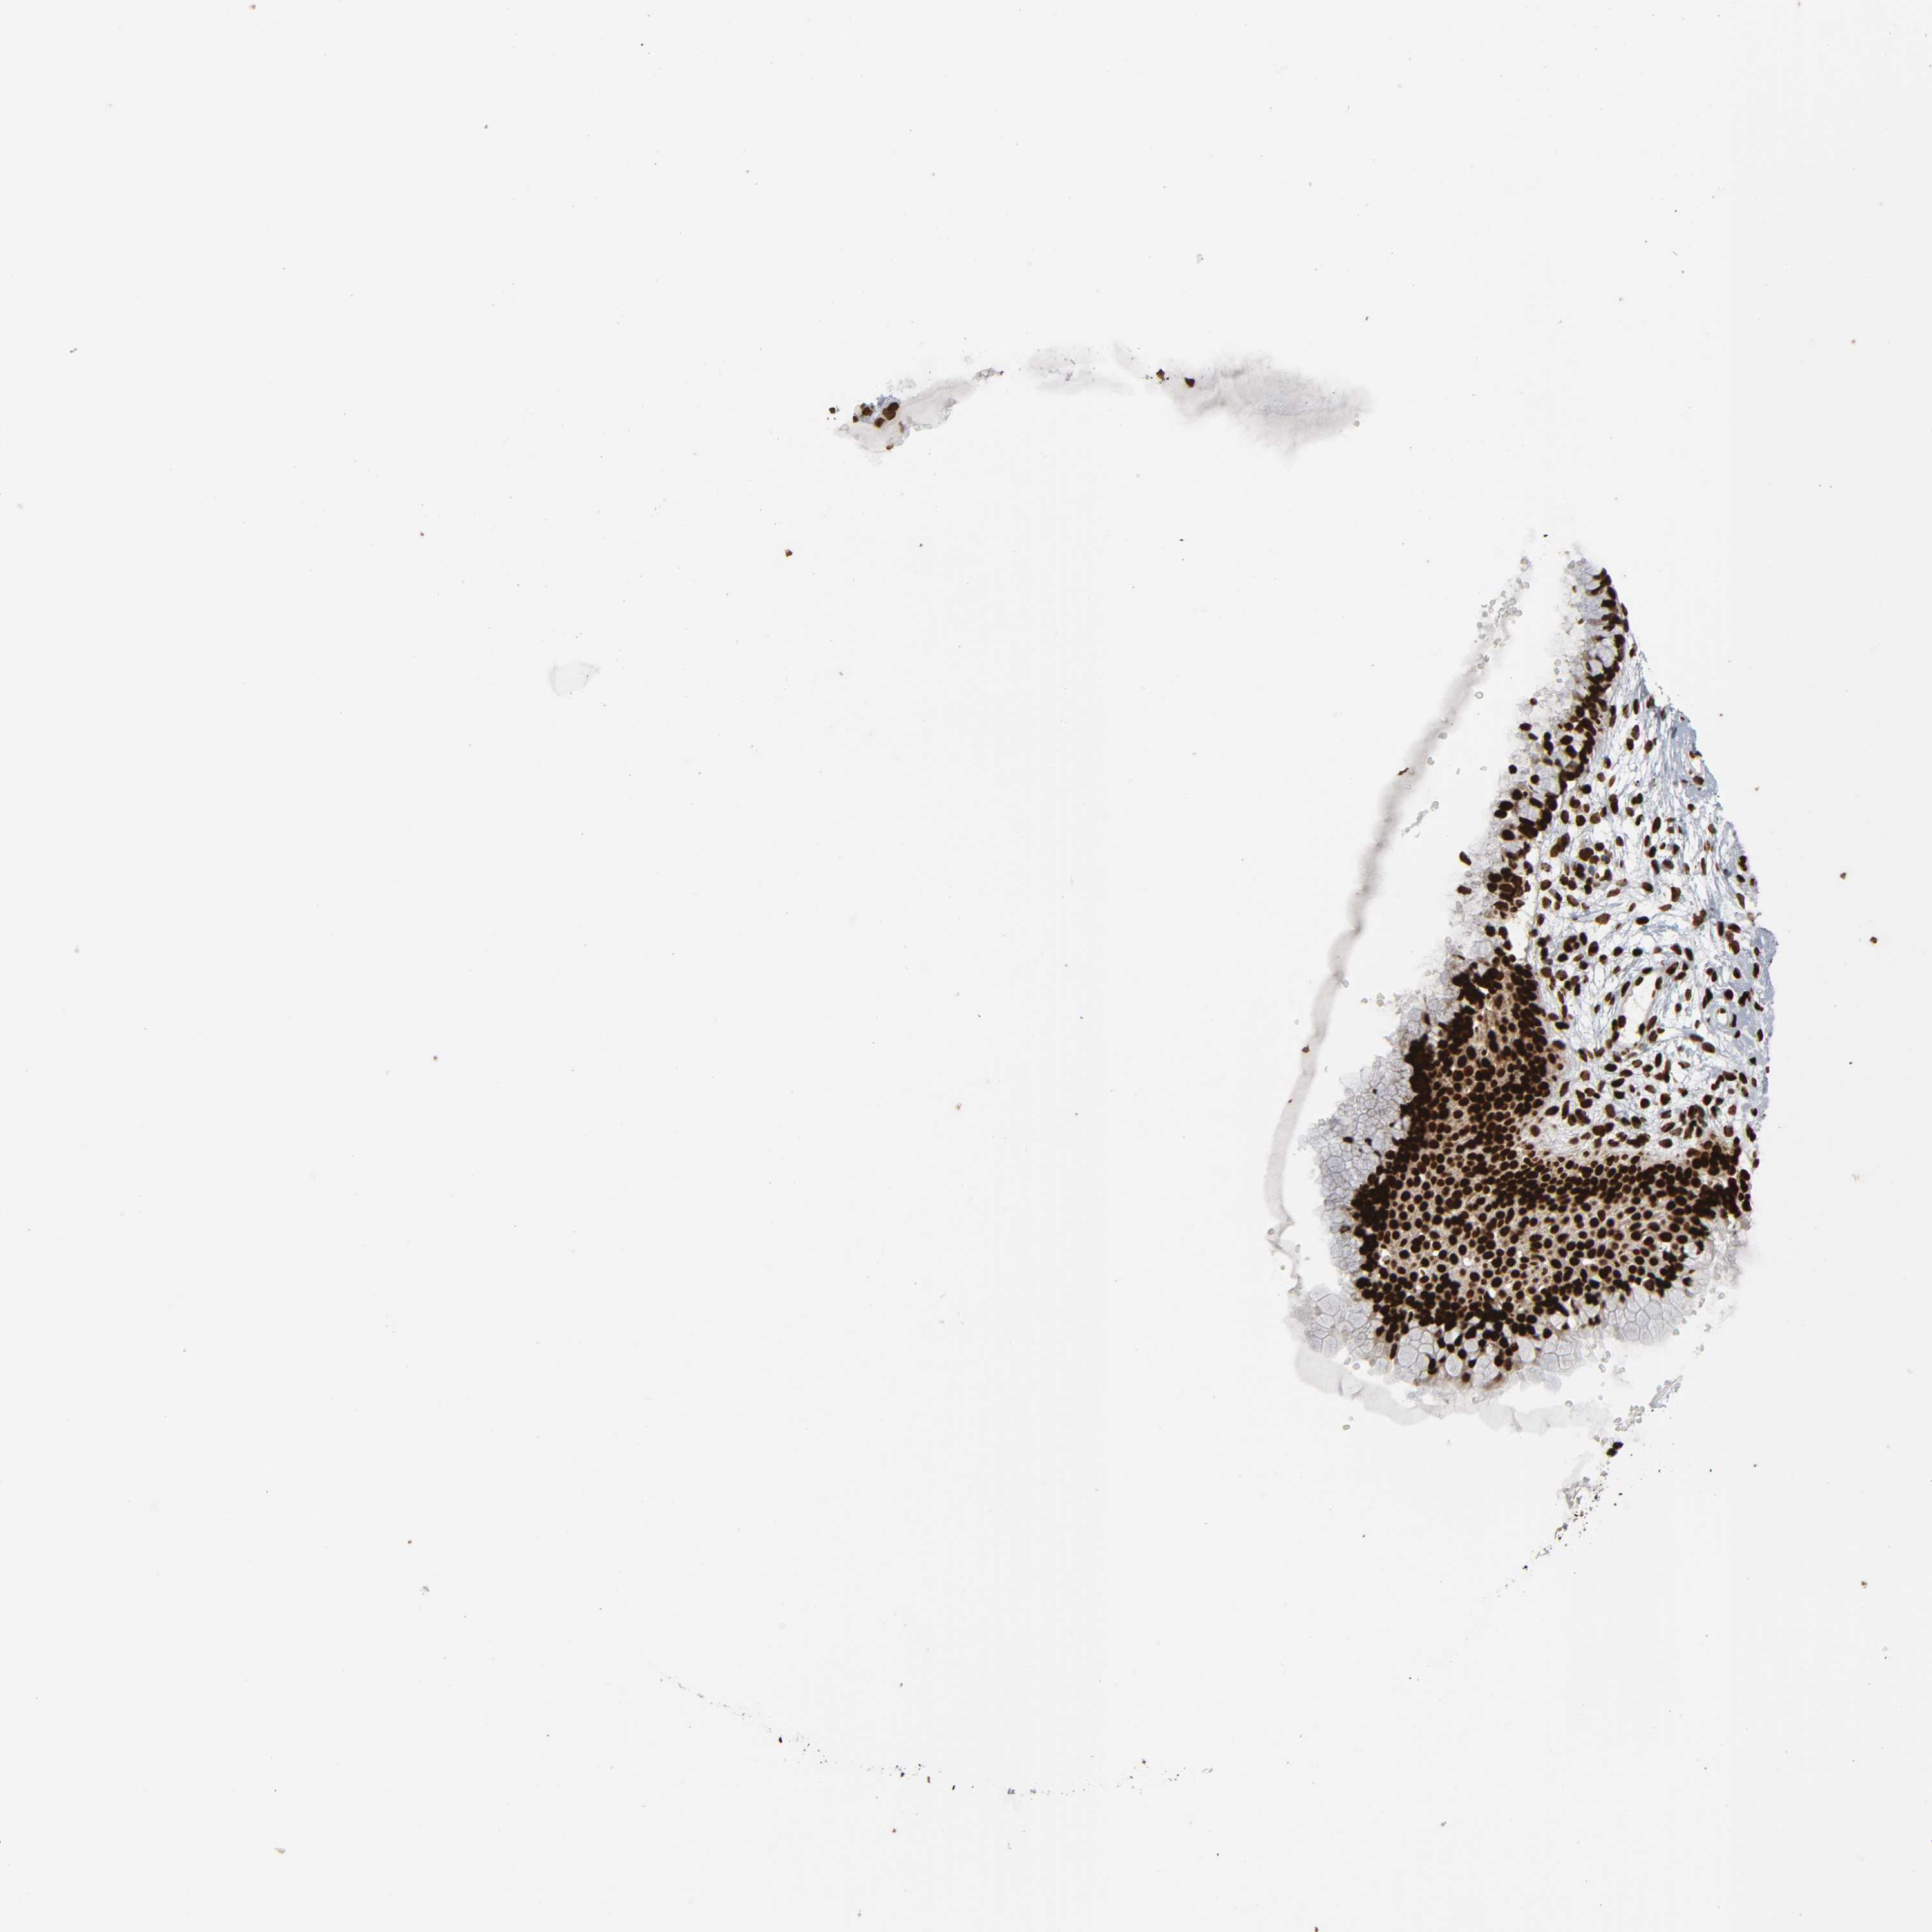

CERVIX - Antibody stainingi

Antibody staining in the annotated cell types in the current human tissue is reported as not detected, low, medium, or high, based on conventional immunohistochemistry profiling in selected tissues. This score is based on the combination of the staining intensity and fraction of stained cells.

Each image is clickable and will lead to virtual microscopy that enables deeper exploration of all samples and also displays staining intensity scores, fraction scores and subcellular localization as well as patient and tissue information for each sample.

Antibody CAB004565Antibody CAB005352

Glandular cells HighMedium

Squamous epithelial cells MediumHigh